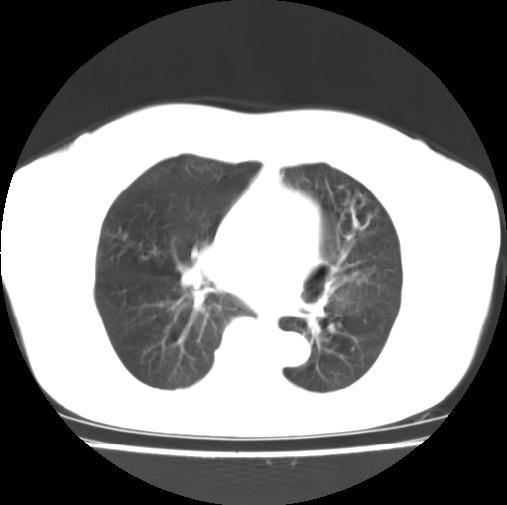

女性病人,56岁,反复咳喘30余年,伴大量脓痰,偶有痰中带血。

此病例在科室里有较大的争议,我认为是先天性肺囊肿(理由是:两者起病年龄都较轻,都有咯血及脓痰的症状,而先天性肺囊肿壁薄;而支扩的囊腔旁一般都能看到伴行的血管影,形成“印戒”征)。以上为个人的意见,请高手们指点一下。

影像符合支气管扩张伴感染,先天肺囊肿壁薄,而后天支扩因反复感染壁多较厚,有慢性支气管炎病史。最后诊断靠病理,先天肺囊肿的囊内无尘埃。

本例应为支气管扩张并感染,与囊肿区别在于其大小,分布,壁改变,与肺动脉关系,形态等来鉴别,要点大家都说得差不多了,囊肿要大些,分散些,靠外围一些,而支扩靠内一些,聚拢些,小一些且易聚拢呈葡萄状,不能单从囊壁厚度来评价,特别是有粘液栓类的改变更加支持支扩,有时支扩亦与囊肿混在一起并存.个人意见仅供参考.